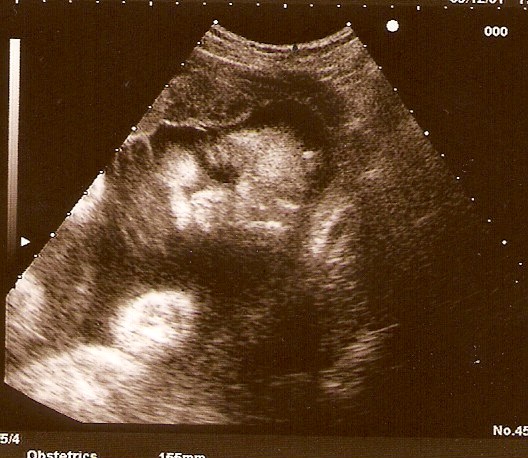

már nem volt levegőm. De legalább csak egy sebbel megúsztam a műveletet, pedig még tükröt is használtam, hogy minél tökéletesebb legyen az eredmény, mivel tudtam, hogy a dokinő meg fogja kukkolni. Megvolt a nagy méretkezés, az uh-on megnézegettük a kis csöppömet, aki nem is olyan kis csöpp.

Na szóval a méretei 29+6 naposan:

BPD: 80 mm

FL: 60,9 mm

AC: 259,5 mm

Súlya: 1682 g

Az uh-n fejvégű fekvésben volt, de nem hiszem, hogy állandóan így van, mikor annyifelé szoktam érezni a mocorgását.

Állítólag jó nagy a lepényem, ezért még rengeteget fog nőni. De könyörgöm hova, már így is olyan nehéz néha a poci! Na meg hogy fog kiférni a nem óriás alkatomból???!!! Bele sem merek gondolni.

Sajna, nem 4D gépen vizsgált, így csak képeket kaphattam róla. Ígérem majd bepróbálkozom, hogy ide is tudjak tölteni egy képet.